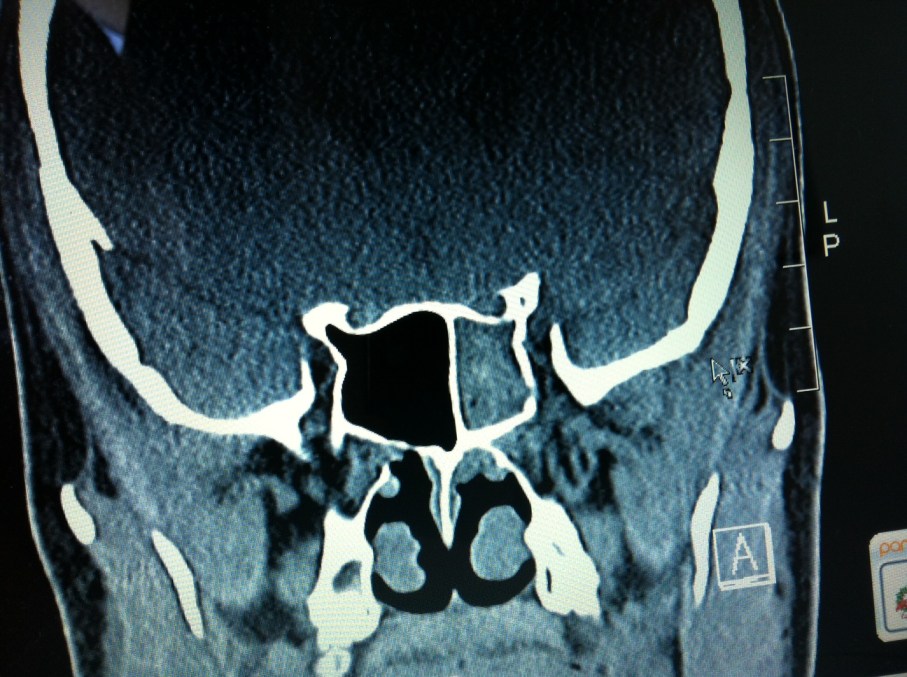

The right side of the pic is actually my left side. You can see how the big honkin’ sinus on my right is a nice black hole, which it should be. The left one is completely blocked. Here’s another shot:

Again, you can see the left sinus is totally blocked. That would explain most if not all of the pain I was experiencing! Hopefully the anti-biotics he put me on will clear it up quickly.